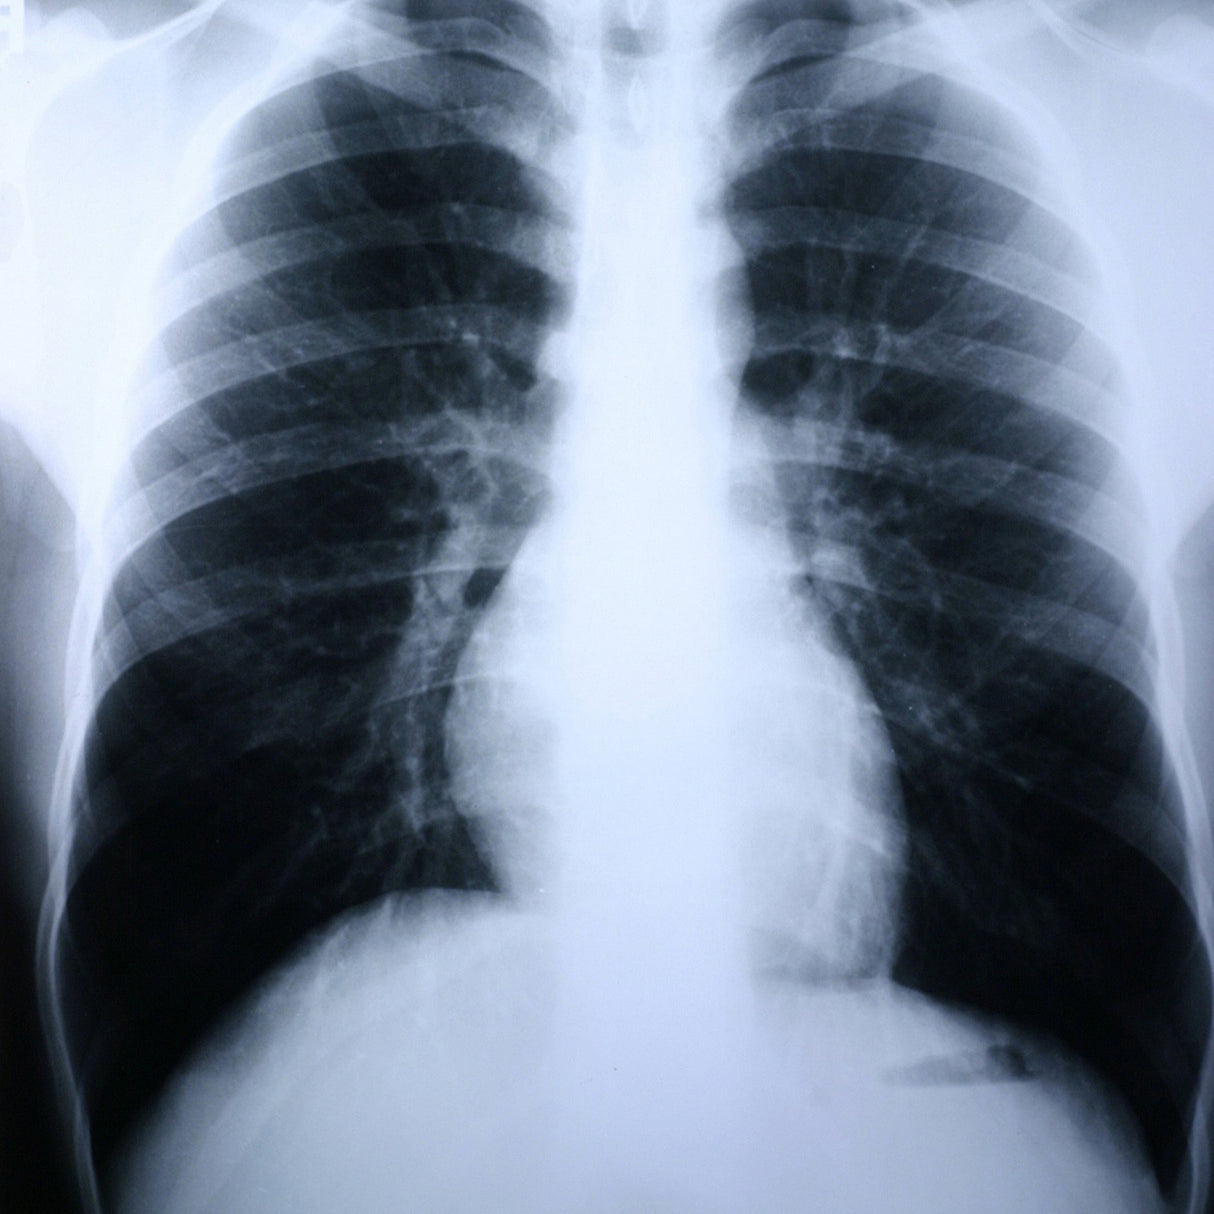

X-Ray Film Clear Choice™ Performance 10 X 12 Inch Medium Speed Green Sensitive High

X-Ray Film Clear Choice™ Performance 10 X 12 Inch Medium Speed Green Sensitive High - Box of 100 está agotado y se enviará tan pronto como vuelva a estar disponible.

- Green

- 10 x 12 Inch (25.4 x 30.5 cm)

- High contrast orthochromatic film designed for general radiography using green emitting intensifying screens.

- Enhances image sharpness with high resolution for general radiography and special procedures.

- For use with Green Rare Earth Screens.

- Made in the U.S.A.